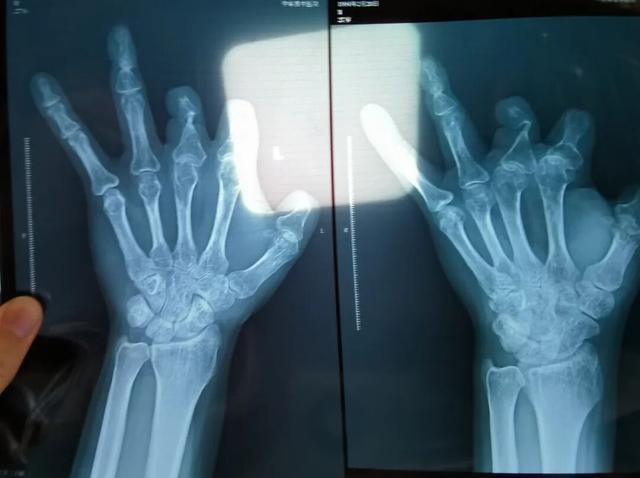

患者王海森左手拇指关节以上部位被电锯切断,收费单显示术中使用了微血管吻合装置,但X光片中未显示该器械。新京报记者 程亚龙 摄

装置上带有不锈钢针,不可能被人体吸收,唯一的可能就是“手术时其实没有使用”。尽管之前也有其他人向王海森透露过这一点,但直到看到片子前,他一直都不相信。

单价1.68万元,声称在术中植入体内、用于缝合血管的两个环形吻合装置,竟然在王海森的X光片上消失了。

2021年12月,患者彭先生拍摄的左手X光片,未见收费单据中列出的微血管吻合装置。新京报记者 程亚龙 摄

该产品的代理商曾向新京报记者证实,微血管吻合装置为植入型医疗器材,患者拍摄X光片时会有显示。新京报记者获取了一位曾在郑大一附院接受手术、使用了该产品的患者的X光片,其手术部位可见一绿豆大小的光圈。